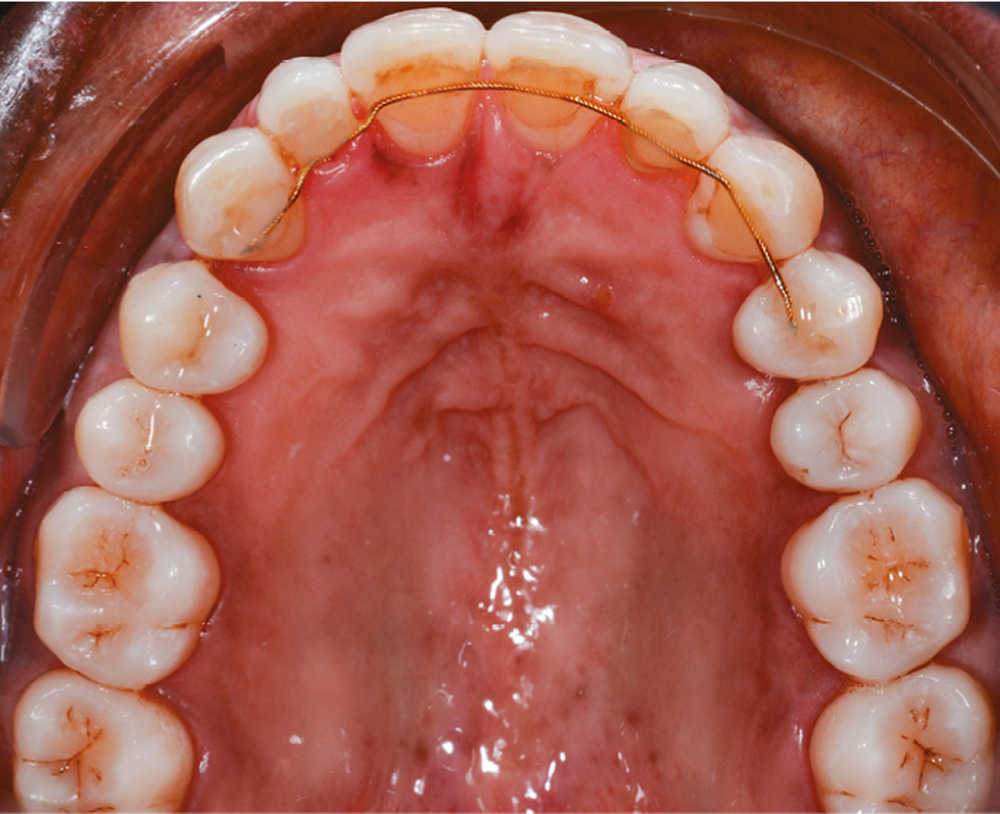

L’observation clinique après traitement parodontal initial révèle, au niveau interarcade, des rapports de classe I molaire bilatéraux associés à des rapports de bout à bout incisif. Dans la dimension verticale, elle présente une légère infraclusion antérieure. On ne note pas d’anomalie de la dimension transversale (fig. 3 à 5). À l’examen intra-arcade, on constate des diastèmes maxillaires interincisifs (1 mm), en distal de 13 (0,5 mm) et de 24 (1 mm) ainsi que des malpositions unitaires (linguoversion de 12, rotation mésio-vestibulaire disto-linguale de 24). À la mandibule, on observe une couronne céramométallique au niveau de 32 plus large de 1,5 mm que les autres incisives ainsi qu’une rotation mésio- linguale de 35 (fig. 6 à 8). En diduction, on note une interférence au niveau de 24.